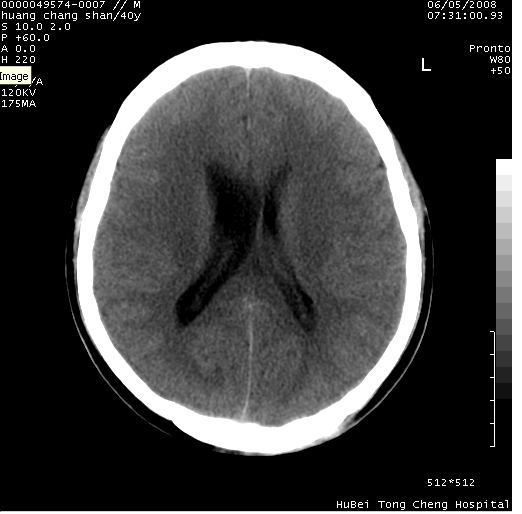

患者 m,40y。头痛,视力模糊,多饮多尿,性欲减退半年余。

行ct平扫+增强,图象如下:

肿瘤强化明显、鞍部骨质结构未见增大、破坏,考虑脑膜瘤可能性大

鞍背无破坏和明显受压,病变明显均匀强化,边界清晰。鞍上区脑膜瘤可能性大,不除外生殖细胞瘤。

平扫病灶呈等密度,增强后强化明显,均匀一致,结合病史首先考虑:垂体瘤。脑膜瘤不支持,因为脑膜瘤平扫多为实性呈均匀高密度影像,内分泌症状多不明显,垂体内分泌素测定正常。

鞍上池肿瘤,鞍背及垂体窝形态变化不明显,病灶强化密度均匀且高度强化,考虑实性颅咽管瘤、生殖细胞瘤及脑膜瘤可能。

结合临床考虑鞍上生殖细胞瘤可能性大于脑膜瘤(增强未见脑膜围征),建议结合冠状位扫描看病灶起源及垂体窝、鞍底情况。垂体窝内未见明显软组织密度影,垂体窝未见扩大,暂不考虑垂体瘤;病灶较大,未见囊变及钙化,颅咽管瘤不支持。期待结果!

1、头痛,视力模糊,多饮多尿,性欲减退半年余,提示:肿瘤为功能性肿瘤。

2、ct表现:肿瘤呈类圆形,均匀略高密度,无囊变,无钙化。侧脑室有扩大。

3、首先考虑:功能性垂体大腺瘤。

4、鉴别诊断:脑膜瘤,瘤体内点状钙化最具特征性,常位于鞍结节。颅咽管瘤,蛋壳样钙化,常有囊变。动脉瘤,位于鞍旁,强化与动脉一致。有时尚需与发生于鞍区的生殖细胞瘤鉴别,生殖细胞瘤钙化亦较常见。

5、友情提示:下回发现鞍区占位性病变,最好加扫冠状位,了解肿瘤与蝶鞍的关系及蝶鞍骨质的改变。